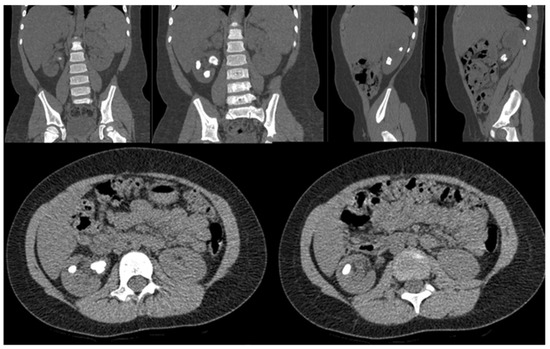

The more problematic elements represented by the more hidden location of the pelvis and the difficulty in locating the course of the ureter and renal vessels are solved by the dexterity of robotic instruments and 3D vision (Figure 3). These distinctive aspects of robot-assisted surgery are found to be even more critical in the second stage of the procedure, that of joint reconstruction, where they facilitate the surgeon’s work and make the anastomosis safer.

Figure 3.

A case of a patient with a horseshoe kidney in which the renal pelvis is hidden (A). The great freedom of movement of the robotic instruments allows them to reach the pelvis (B) and perform pyeloplasty with ease (C).